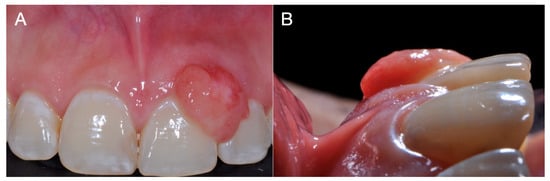

Intraoral clinical examination identified an increase in the volume of the gum (measuring 1.0 cm × 0.7 cm × 0.3 cm) located between the central and upper left lateral incisors, and partially filling the vestibular space. On palpation, the area presented a soft consistency, a rough texture, an oval base with slight mobility, and a pink coloration with irregular margins but without bleeding or pain (Figure 1). Furthermore, a probing depth of 9 mm was recorded vestibularly. Subgingival calculus and plaque were present. Contradictorily, there were no signs of dental mobility and the patient referred no symptomatology. Intra-oral peri-apical radiograph revealed no pathological findings or any signs of bone loss, root resorption, or increased periodontal ligament space (Figure 2). A complete blood count was performed and all blood results were within normal limits. Based on the information obtained from the historical, clinical, and radiographic examinations, a presumptive diagnosis of pyogenic granuloma or PGCG was considered.

Figure 1. Preoperative clinical view of PGCG in the patient, showing an increase in gum volume corresponding to the circumscribed and well delimited lesion between maxillary central and lateral incisors. (A) Frontal view; (B) lateral view.